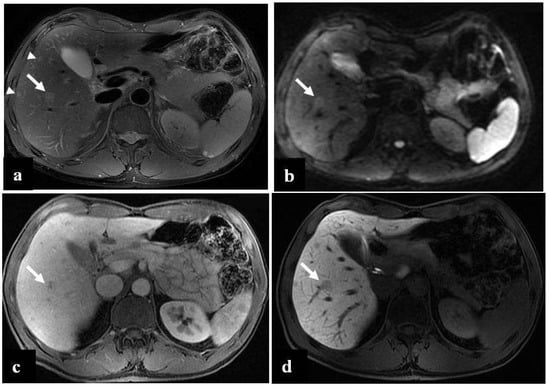

Figure 1.

(a–d) A 68-year-old woman with liver metastases from colon cancer undergoing neo-adjuvant chemotherapy with 5-fluoroacil and irinotecan (FOLFIRI). After chemotherapy, the axial T1-weighted in-phase image (a) showed diffuse hyperintensity of the liver with two adjacent hypointense metastatic lesions in segment 4, and the axial T1-weighted opposite-phase image (b) demonstrated a loss of signal at the level of the non-tumoral-bearing liver parenchyma, suggesting hepatic steatosis; moreover, the metastatic lesions appeared bright relative to the steatostic liver. About a year after the last chemotherapy and after resection of liver metastases, on MRI, no differences were found in the signal intensity between the axial T1-weighted in-phase image (c) and opposite-phase image (d) at the level of the liver parenchyma; therefore, we deduced that the steatosis was resolved.